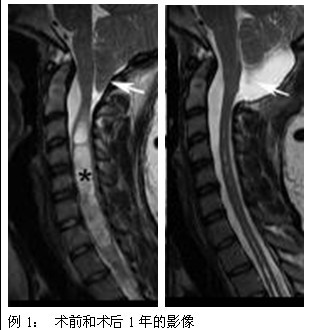

本病的发病机理尚未完全阐明,目前比较为大家所接受的观点基本均认为脑脊液动力异常是该病继发脊髓空洞的动因。因此,改变异常的解剖结构、恢复脑脊液的正常动力学状态已成为外科干预的主要方式。事实证明,外科治疗可以使大多数空洞的状况得以改善,已经形成的空洞可以停止发展,甚至消失。

(1)颅颈交界区减压手术:通过手术解除环枕区骨性结构对小脑、脊髓等结构的压迫,从而恢复正常的脑脊液动力学循环通路,从病因的角度对该病进行治疗。